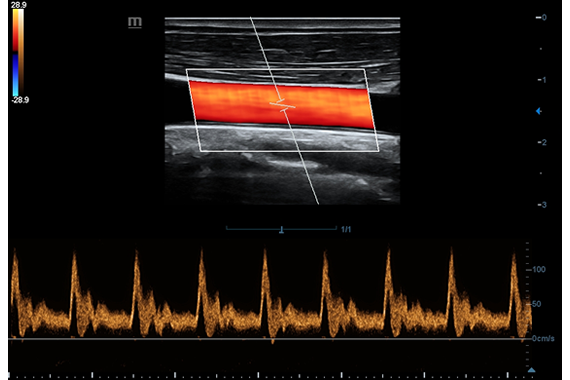

• HR Flow - режим отображения кровотока с высоким временным и пространственным разрешением для точной и однородной визуализации сосудов, в том числе самых мелких.

Цветовой допплер:

Да

Импульсно-волновой допплер:

Дуплексное сканирование: